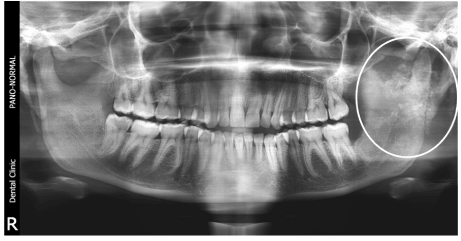

An OPG revealed flocculent snowflakes like radio-opaque mass superimposed on left side of ramus of mandible with no sign of resorption of mandible (Figure 2). Differential diagnosis of chondroma, chondro-sarcoma, progressive myositis ossificans, cemento -ossifing fibroma, pleomorphic adenoma with calcification in PPS were considered. With above mentioned clinical and radiographic diagnosis patient was advised contrast MRI scan which showed large, well circumscribed, encapsulated soft tissue lesion measuring approximately (6.0 × 5.5 × 5.2 cm) epicentered in left parapharyngeal space extending cranially into infratemporal fossa with close proximity to middle cranial fossa and displacement, distortion of nasopharyngeal, oropharyngeal air space was also observed. The fat planes between the mass with deep lobe of parotid gland on T1 images were fairly preserved (Figure 3). On contrast study predominantly heterogeneous shaggy peripheral and multiple patchy area of blooming was suggestive of intra-tumoral calcification and Carotid sheath was displaced postero-laterally by mass. MRI images reported that mass maybe soft tissue fibro-osseous lesion, extraosseous osteosarcoma, chondroma, chondrosarcoma or benign minor salivary gland tumor with large amount of calcification.

Figure 2. Flocculent snowflakes like radio-opaque mass superimposed on left side of ramus of mandible in OPG.